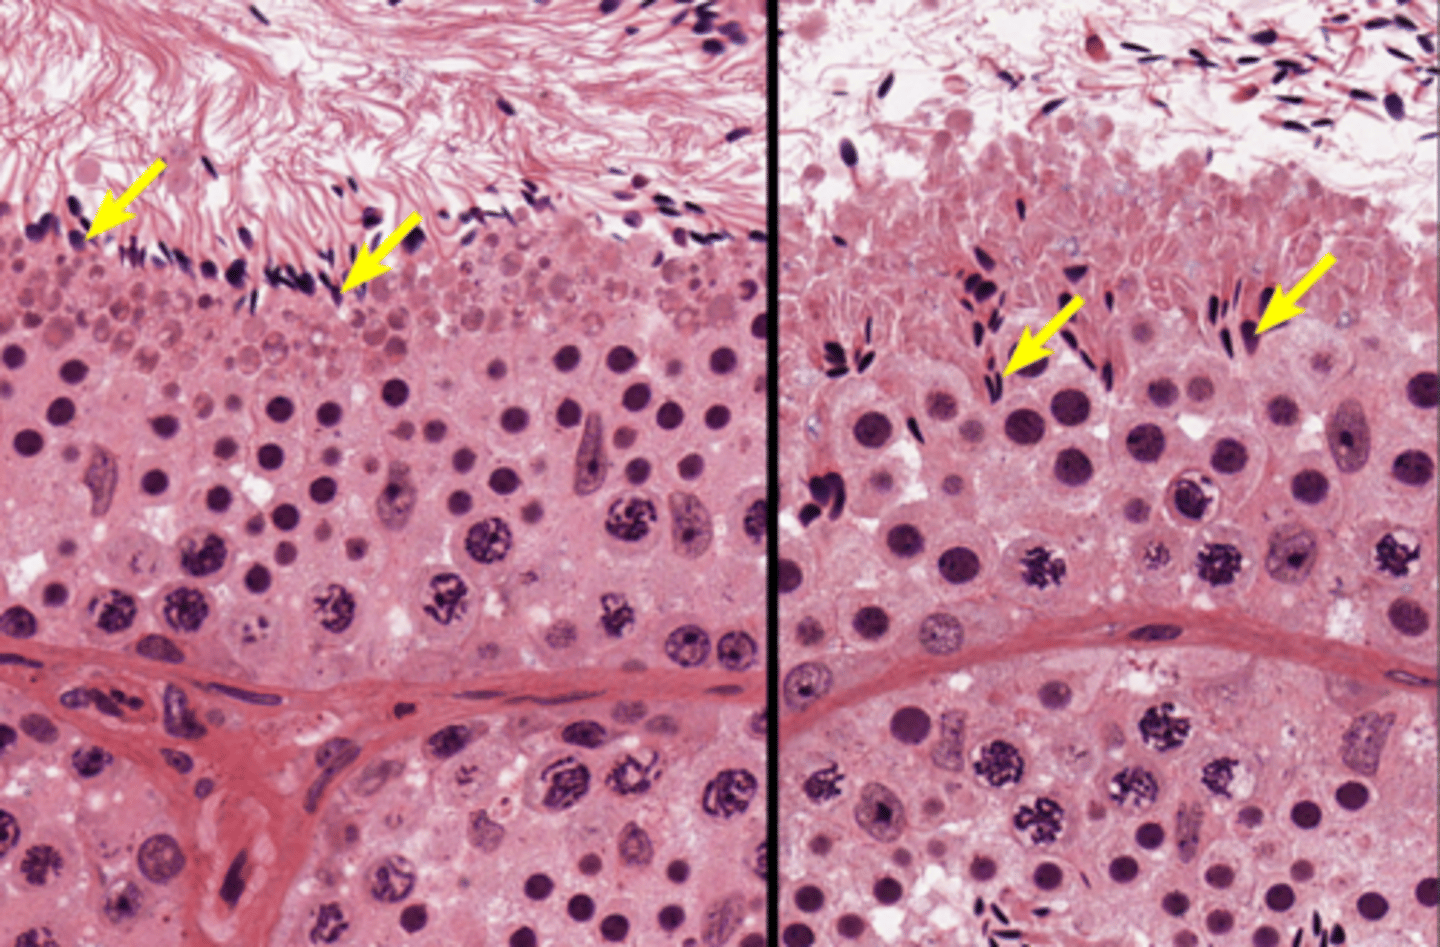

Seminiferous tubules

Seminiferous tubules

Seminiferous tubules

Spermatogenesis

Spermatogenesis

Spermatogonia

Primary spermatocyte

Primary spermatocyte

Spermatid (early)

Spermatozoon